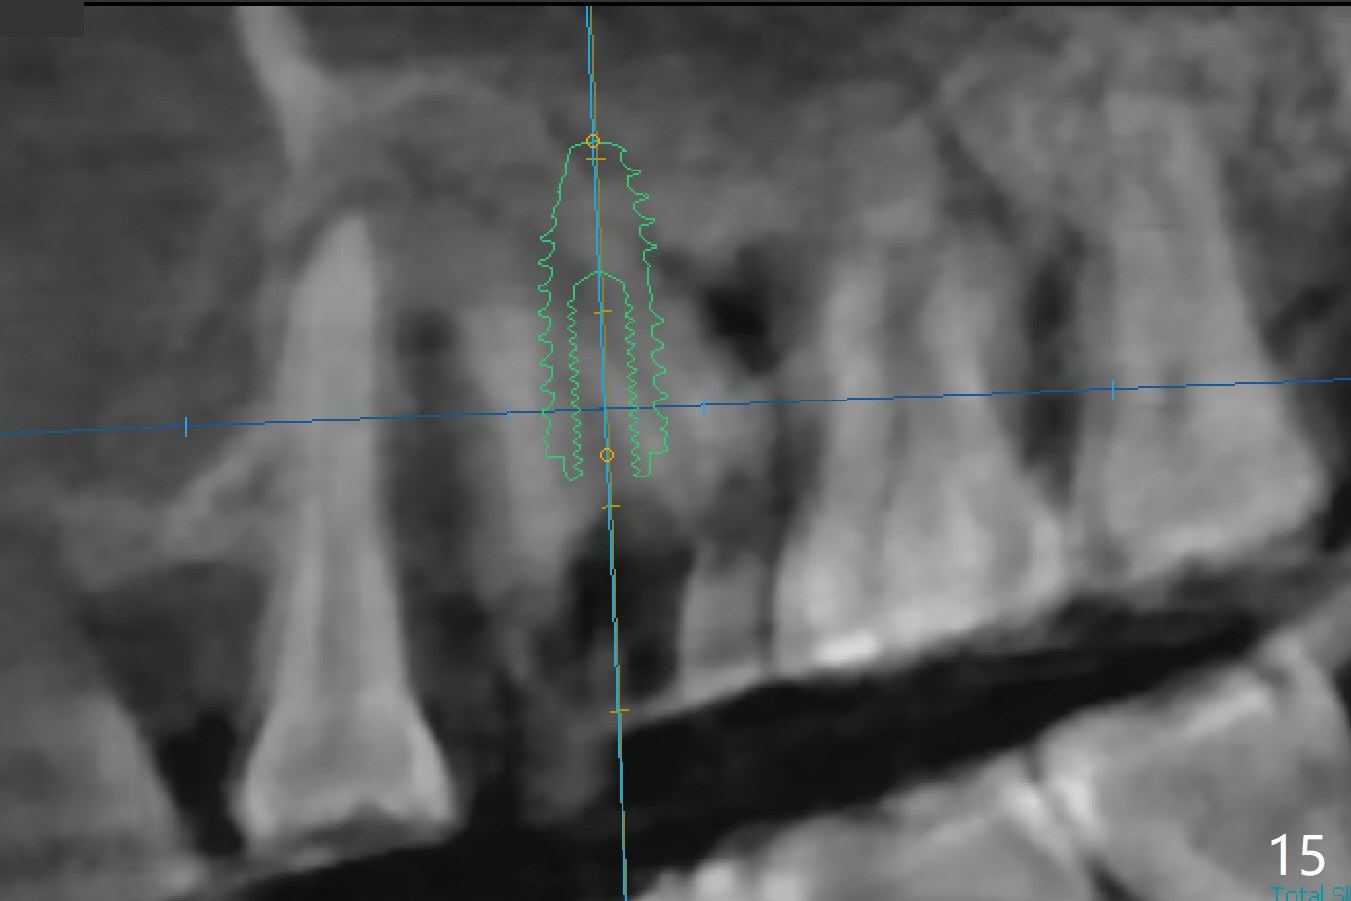

There is more bone apical to the residual root at #13 (Fig.1 red line). An immediate implant along the long axis of the root can be longer, 11.5 mm, favorable for primary stability (Fig.2 (CT taken immediately preop)). The initial trajectory is not ideal (Fig.3). When the pointed/Lindamann bur is removed (Fig.4), effort is made to move the apical end of the osteotomy distal (Fig.5 red arrow) by removing the apical bone (red dashed line). Following sequential osteotomy, a 4x10 mm dummy implant is placed with the trajectory remaining not so ideal (Fig.6,7). As the dummy implant is removed (Fig.8), a new osteotomy is established distal to the existing one (Fig.9). Subsequent drills gradually shift into the original osteotomy (Fig.10 red arrow). When the same dimension dummy implant returns, the trajectory improves with decreased stability (Fig.11). It seems reasonable to place a larger implant without further osteotomy. After placing PRF membrane and Vanilla graft for sinus lift (Fig.13 *), a 4.5x10 mm definitive implant is placed with loss of control in the trajectory (Fig.12,13).

When the initial osteotomy is off substantially (Fig.4), an osteotomy should be established de novo and as early as possible (Fig.14) so that subsequent osteotomy will not relapse to a great extent. More ideally, the initial osteotomy should be planned correctly (Fig.15,16) with sacrifice of the bone height. Nearly 1 month postop, the 4.5x5.5(5) cementation abutment is loose. When it is removed, the patient feels pain from the implant. A 5.5x6 mm healing abutment is placed instead. The implant osteointegrates with trabecular pattern in the sinus 9 months postop (Fig.20 *). The gingiva around the crown at #13 is healthy 1 year 4 months post cementation (Fig.18). Check the distal surface of #13 for bone loss if the tooth #14 is to be extracted.